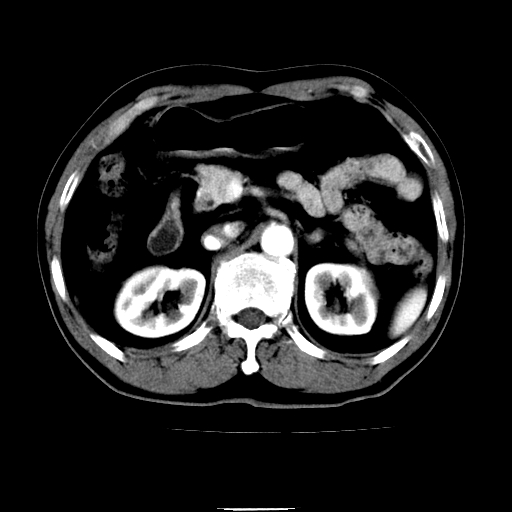

以下是引用chenqiong在2010-3-25 20:56:00的发言:[br]1、胆囊炎,胆囊息肉[br]2、肝内胆管及胆总管扩张,胆总管下端结石[br]3、十二指肠乳头旁憩室

以下是引用zxl51642在2010-3-26 10:47:00的发言:[br]胆囊炎,胆囊息肉,胆总管扩张,但未看到明显肿块,肝内胆管扩张不像恶性,炎性狭窄或阴性结石可能吧,建议mrcp,右肾小囊肿